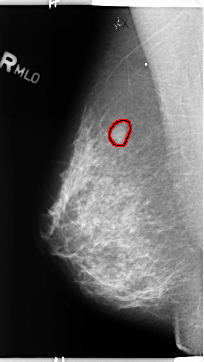

B_3142_1.RIGHT_MLO

RIGHT_MLO LINES 4696 PIXELS_PER_LINE 2648 BITS_PER_PIXEL 12 RESOLUTION 50 OVERLAY

FILE: B_3142_1.RIGHT_MLO.OVERLAY

TOTAL_ABNORMALITIES 1

ABNORMALITY 1

LESION_TYPE MASS SHAPE OVAL MARGINS CIRCUMSCRIBED-OBSCURED-ILL_DEFINED

ASSESSMENT 4

SUBTLETY 3

PATHOLOGY BENIGN

TOTAL_OUTLINES 1

BOUNDARY